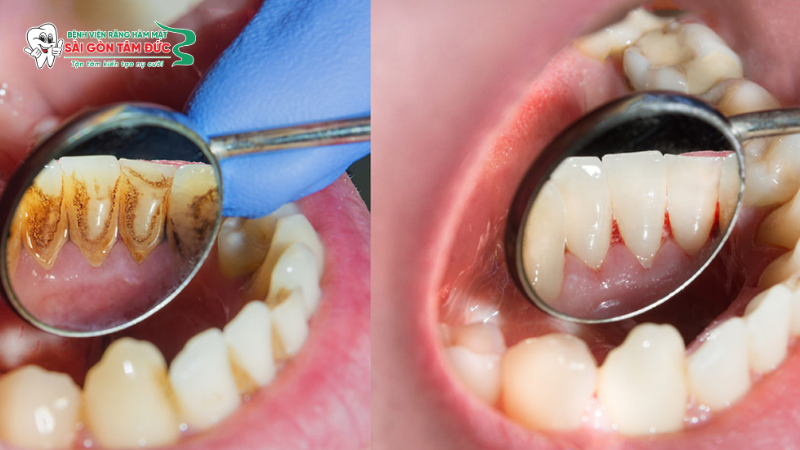

Vôi răng (hay còn gọi là cao răng) là những mảng bám cứng chắc màu vàng nhạt, nâu hoặc đen bám chặt trên bề mặt răng và dưới viền nướu. Quá trình hình thành bắt đầu từ lớp màng sinh học (Biofilm) mỏng chứa vi khuẩn và vụn thức ăn bám trên răng sau mỗi bữa ăn.

Nếu không được làm sạch bằng bàn chải hoặc chỉ nha khoa trong vòng 24 – 72 giờ, mảng bám này sẽ phản ứng với các khoáng chất (Canxi, Phosphate) có trong nước bọt và vôi hóa thành những khối cứng xù xì. Lúc này, bạn hoàn toàn không thể làm sạch chúng bằng cách đánh răng thông thường.

Cạo vôi răng (hay lấy cao răng) là một kỹ thuật nha khoa phổ biến nhằm loại bỏ hoàn toàn các lớp vôi cứng đầu bám trên mặt răng và nằm sâu dưới nướu. Khác với việc dùng dụng cụ cầm tay cạo xát thủ công như trước đây, các bác sĩ hiện nay sử dụng hệ thống máy siêu âm (Ultrasonic Scaler) chuyên dụng.

Các đầu tip của máy phát ra sóng siêu âm với tần số rung phù hợp, tạo ra hiện tượng xâm thực làm vỡ các liên kết của mảng bám mà không cần tác động lực cơ học mạnh, kết hợp với tia nước phun liên tục để rửa trôi cặn bẩn ngay lập tức.

• Thẩm mỹ nụ cười: Cạo vôi kết hợp đánh bóng giúp loại bỏ các vết ố vàng do trà, cà phê hay thuốc lá, trả lại bề mặt men răng trơn láng và độ sáng bóng tự nhiên.